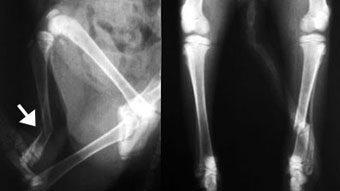

体重4kgの猫の脛骨骨幹部粉砕骨折。

ラグスクリューと細ピンによる骨片安定化とプレート固定術により整復固定しました。

写真上段: 手術前

骨幹部が縦に割れて多数の骨片に分かれています。

写真中段: 手術直後

骨片をラグスクリューと細ピンによりひとつにまとめてから、ほぼ全長にプレートをかけて固定しています。

写真下段: プレート除去後

ラグスクリューなどはそのままとなります。